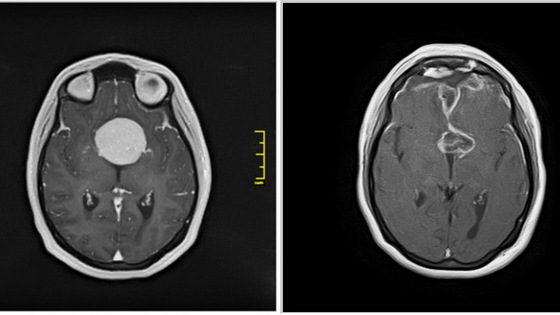

Как сообщает пресс-служба НИИТО, пропадать зрение у пациентки начало после родов в 2016 году. Тогда хуже стал видеть левый глаз. Лечение у офтальмолога не помогало, и постепенно зрение терялось и на правом глазу. Тогда женщина сделала МРТ и выяснила, что у нее в голове гигантская опухоль — менингиома турецкого седла — которая сдавливает и разрушает ее зрительные нервы и обрастает сонные артерии.

Из-за того, что на родине Кристине не смогли помочь, она воспользовалась услугами НИИТО, так как здешняя нейрохирургическая клиника имеет большой опыт в сфере нейроонкологии. В январе 2021 года хирурги НИИТО успешно удалили опухоль.